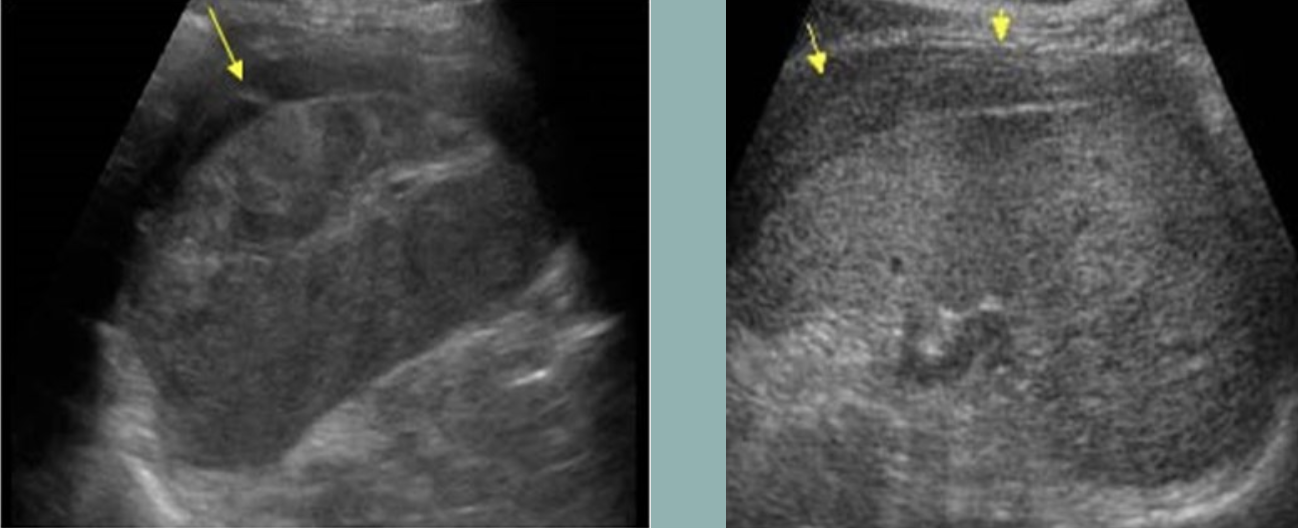

Splenic Infarction → blood supply to section of spleen is interrupted, leads to localized necrosis

clinical hx: infection, cardiac conditions

s/sx: acute LUQ pain, fever

2D US: peripheral hypoechoic wedge extending to capsule, normal adjacent parenchyma, later chronic ± fibrotic echogenic changes, ± splenomegaly

color doppler: avascular

DDX: splenic abscess, hematoma